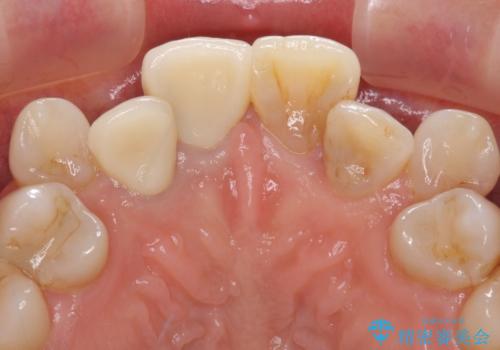

変色した前歯のオールセラミック治療

気になっていた変色が改善され、患者様には大変満足していただきました。